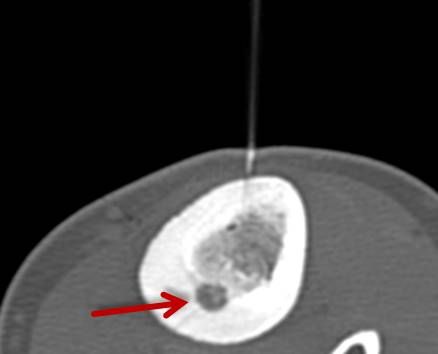

Abbildung: Bei der perkutanen Thermoablation von Lungentumoren werden spezielle Applikatoren unter CT-Bildgebung in den Zieltumor eingebracht. Durch Hitze wird der Tumor dann zerstört.